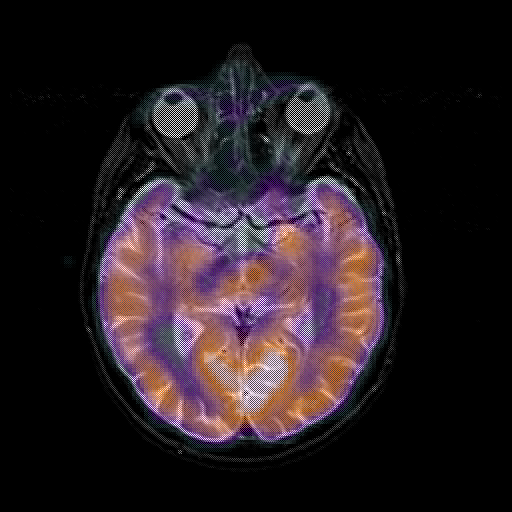

overlay 1: Slice 24

Slice 24